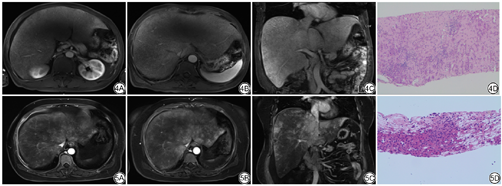

| MR T1WI/T2WI | 肝实质T1WI/T2WI信号均匀、细腻,肝“纹理”(肝实质内细小静脉等所形成的条形及同格样结构)减少(图1)。 | 肝实质T2WI信号不均匀增高,肝内见不规则片状或“云絮”状稍高信号影(图2)。另可见以第二肝门为中心环绕三支肝静脉和下腔静脉的“三叶草”样T1WI稍高T2WI稍低信号影 |

门脉期 | 肝实质强化峰值时间延迟且强化峰值减低,肝实质强化呈“窗凌花”样(图4) | 环绕三支肝静脉和下腔静脉的“三叶草”样强化,余肝实质“地图样”强化(图5) |

延迟期 | 局灶性强化减低灶,与平扫低密度区对应。肝实质强化呈“窗凌花”样 | 肝实质仍呈“地图样”或“花斑样”强化,强化范围较门脉期进一步增大 |

肝淀粉样变性较肝窦阻塞综合征更为罕见,影像学上肝淀粉样变性部分影像特征又与肝窦阻塞综合征影像特征相似,肝淀粉样变性容易被误诊为肝窦阻塞综合征。两种疾病的相似之处为CT平扫肝实质密度均为不均匀减低,增强扫描肝脏静脉期的不均质强化,似“地图样”改变,三支肝静脉常未见显影或显影纤细。笔者通过研究将两者的影像学鉴别总结如下:(1)肝淀粉样变性患者多表现为巨肝,大多患者不伴有腹水;而肝窦阻塞综合征患者肝脏体积则呈轻度增大,多伴有大量腹水。(2)肝淀粉样变性MRT2WI上肝实质信号均匀、质地细腻,与正常人肝脏T2WI像(图3)比较,肝“纹理”(肝实质内细小静脉等所形成的条形及同格样结构)减少;此特点的描述借鉴于国内郭勇等[13]的研究。而肝窦阻塞综合征MRT2WI信号呈不均匀增高,肝实质内可见不规则片状或呈“云絮”状稍高信号影,另可见以第二肝门为中心环绕三支肝静脉和下腔静脉的“三叶草”样T1WI稍高T2WI稍低信号影,此征象与国内外大多学者的研究也相符[14, 15, 16, 17, 18]。(3)肝淀粉样变性增强三期扫描发现肝实质强化峰值时间延迟且强化峰值减低,门脉期及延迟期强化欠均匀,门脉期及延迟期肝内可见多发的局灶性的强化稍减低灶,以门脉期为著,门脉期及延迟期的肝脏某种程度上像北方秋冬季节水蒸气遇冷后凝集在玻璃上的“窗凌花”(4A、4B、4C)。而肝窦阻塞综合征增强扫描静脉期肝实质呈“三叶草”样及“地图样”强化(5A、5B、5C)。(4)肝淀粉样变性患者肝动脉代偿性增粗,其增粗程度[6.00±0.39(n=8)]较肝窦阻塞综合征患者[4.00±0.83(n=20)]有统计学差异,产生此现象的病理生理机制尚不清晰,有待进一步研究。(5)肝淀粉样变性患者累及脾脏、肾脏亦十分常见,影像上除了肝脏的异常影像表现外,可伴有脾脏及肾脏的淀粉样物质沉积造成的脾脏或(和)肾脏的低血流灌注状态。本组8例增强患者同时伴脾脏低灌注强化差的有7例(87.5%),同时伴有肾脏灌注差的有2例(25%)。(6)肝窦阻塞综合征患者大都伴有食管胃底静脉呈轻度曲张,胆囊壁增厚水肿(>3 mm)。肝淀粉样变性患者未见此征象。